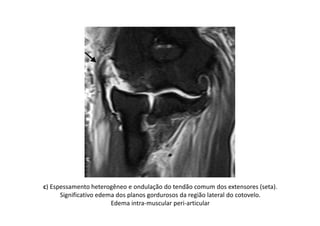

c) Espessamento heterogêneo e ondulação do tendão comum dos extensores (seta).

Significativo edema dos planos gordurosos da região lateral do cotovelo.

Edema intra-muscular peri-articular